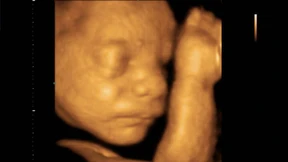

Markus Heckemann betreibt „Babyfacing, ein Fotostudio für ungeborene Kinder. Hier gibt es Ultraschall ohne medizinischen Anspruch, nur um Erinnerungsfotos vom ungeborenen Kind im Mutterleib zu machen.